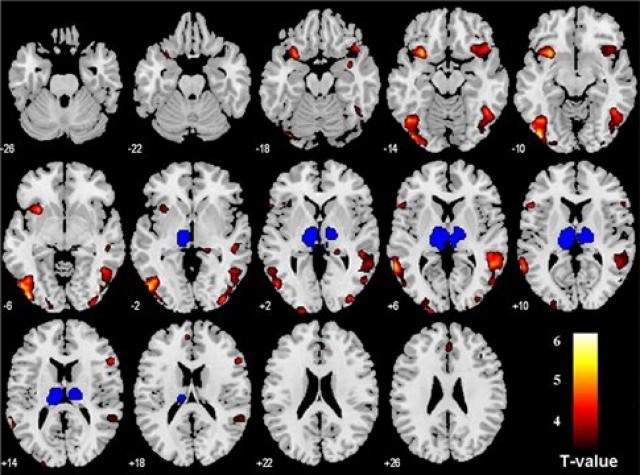

Επιστημονική ομάδα του Ινστιτούτου Γνωσιακής Νευροεπιστήμης του Πανεπιστημίου του Λονδίνου, με επικεφαλής τον Δρ Τζόναθαν Ρόιζερ, υπέβαλλαν σε λειτουργική μαγνητική εγκεφαλική απεικόνιση (fMRI) 23 εθελοντές, ώστε να μπορέσουν να μελετήσουν καλύτερα την λειτουργία της ηνίας, μια εγκεφαλική δομή όχι μεγαλύτερη από ένα μπιζέλι.

Οι ερευνητές ζήτησαν από τους εθελοντές να κοιτάξουν μια σειρά από εικόνες και, ύστερα από λίγα δευτερόλεπτα, μερικές εικόνες συνοδεύονταν από ήπιο ηλεκτροσόκ (τιμωρία), άλλες από ανταμοιβή (χρήματα) και οι υπόλοιπες από τίποτε από τα δύο. Αφού οι συμμετέχοντες είχαν πια μάθει να συσχετίζουν μια εικόνα με ένα μελλοντικό αρνητικό, θετικό ή ουδέτερο ερέθισμα, διαπιστώθηκε ότι κάθε φορά που έβλεπαν την εικόνα που είχε συνδεθεί με το επερχόμενο ηλεκτροσόκ, ενεργοποιούνταν η περιοχή της ηνίας στον εγκέφαλό τους.

Οι επιστήμονες υποστηρίζουν ότι, η εν λόγω περιοχή εξελίχτηκε για να βοηθά τα ζώα -και τους ανθρώπους- να μαθαίνουν από τις άσχημες εμπειρίες τους, έτσι ώστε να τις αποφεύγουν έγκαιρα στο μέλλον. Όμως αυτή η αντίδραση, αν είναι υπερβολική, μπορεί να δημιουργεί υπερβολική ανησυχία, απαισιοδοξία και τελικά κατάθλιψη.